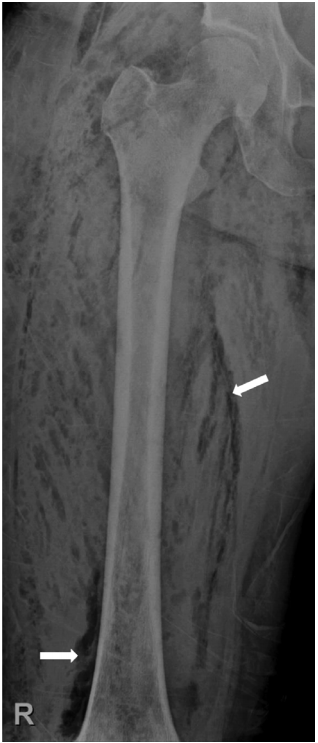

환 자: 57세 여자주호소: 오른쪽 무릎 통증과 부종현병력: 내원 7일 전 가위에 오른쪽 무릎을 찔린 후 2일째 부터 무릎 통증이 발생하여 동네 병원을 방문해 화농성 관절염의 진단 하에 항생제 치료를 하였으나, 무릎 통증과 부종, 발열 등의 임상증상이 호전되지 않고 악화되어서 본원으로 내원함과거력: 8년 전 고혈압과 당뇨병으로 진단받은 후부터 약물치료 중이며, 같은 해에 자궁근종으로 자궁절제술을 시행함가족력/사회력: 특이소견 없음이학적 소견: 응급실 내원 당시 혈압 120/64 mmHg, 맥박 99회/분, 호흡수 24회/분, 체온 38.5℃였다. 의식은 명료하고 급성 병색 소견을 보였다. 오른쪽 무릎과 넓적다리에 부종, 발적과 함께 열감, 압통, 마찰음(crepitus)이 촉지되었다.검사실 소견: 말초혈액 검사에서 백혈구 10,200/mm2 (호중구 85.8%)로 증가되어 있었고, 혈색소 8.2 g/dL로 감소되어 있었으며, 혈소판 182,000/mm2로 정상이었다. 생화학 검사에서 아스파르테이트아미노전달효소(AST)가 50 IU/L (참고치 10-45)로 약간 증가되었고, 알라닌아미노전달효소(ALT) 12 IU/L (참고치 10-45), 알카리인산분해효소(ALP) 72 IU/L (참고치 42-121), 총빌리루빈(T. bilirubin) 0.4 (참고치 0.2-1.2)로 정상 범위에 있었다. 혈액요소질소(blood urea nitrogen) 39 mg/dL (참고치 7-18)로 증가된 반면 크레아티닌(Cr)은 0.6 mg/dL (참고치 0.6-1.2)로 정상이었다. 총단백 4.6 g/dL (참고치 6.5-8.3), 알부민 1.7 g/dL (참고치 3.6-5.5)로 감소되어 있었고, 적혈구침강속도(erythrocyte sedimentation rate) 120 mm/h (참고치 0-20), C-반응단백(C-reactive protein) 238.3 mg/L (참고치 0-5.0)로 증가되어 있었다. 혈청 검사에서 B형간염표면항원과 항체가 모두 음성이었고 C형간염항체도 음성이었다.방사선 소견: 단순 방사선 사진에서 오른쪽 무릎관절 주변과 대퇴부에 가스 음영이 관찰되었고(Fig. 1), 자기공명영상에서는 오른쪽 무릎관절 및 대퇴부의 대부분 근육에 부종과 가스 음영이 관찰되었다(Fig. 2).치료 및 경과: 가스 괴저로 인한 패혈증으로 진단하고 penicillin G 500 M units q 6 hrs, clindamycin 600 mg q 8 hrs 그리고 ceftriaxone 2 g q 24 hrs을 투약하였다. 그리고 응급으로 괴사조직제거술과 세척술을 시행하였는데, 당시 피부절개를 한 후에 확인한 근육병변에서 심한 악취가 났다. 또한 오른쪽 대퇴사두근 중에서 일부를 제외한 대부분의 근육이 괴사가 되어서, 괴사된 대부분의 조직을 제거하였다(Fig. 3). 혈액 배양은 음성이었으며 수술장에서 시행한 괴사조직배양 검사에서 페니실린에 감수성이 있는 Streptococcus anginosus가 배양되었다. 항생제는 ceftriaxone 2 g q 24 hrs과 clindamycin 600 mg q 8 hrs으로 투여하고, 매일 병변 부위를 소독하면서 괴사조직에 대해서 조직제거술을 시행하였다. 수술 후 12일째에 환자에서 발열이 있으면서 수술부위에서 농이 발생하여 농에 대한 배양 검사를 시행하였다. 배양 검사에서 carbapenem-resistant Acinetobacter baumannii가 동정되어서, 항생제는 Imipenem 500 mg q 6 hrs과 Ampicillin/sulbactam 3 g q 6 hrs의 병합요법을 시행하였다. 이후에 발열이 호전되고, 수술병변도 농이 없어지면서 다시 좋아지는 소견을 보였다. 내원 첫날부터 19일간 괴사조직제거술과 세척술을 시행한 후에는 병변에 대해서 소독만 시행하였고, 항생제는 총 59일간 투여하였다. 이후에 다리의 병변 부위가 모두 좋아져서 오른쪽 목발 보행을 위한 재활 치료를 하였다. 재활 치료를 하면서 걸을 때 오른쪽 발을 저는 후유증을 제외한 모든 증상이 호전되어서 71일 이후에 퇴원하였다.